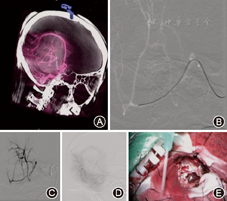

(1)空间大小:复合手术室内设备多且活动性强,手术室所需空间一般应大于常规手术室,一般要求纯手术间的使用面积>70 m2。例如某医院神经血管复合手术室建筑面积120 m2,纯手术间使用面积79 m2。在设定手术间时,应预留一部分空间以便纳入未来更多的血管内治疗、显微外科或其他(如高频聚焦超声)治疗相关设备。(2)层流:手术室必须具备百级洁净度层流条件。(3)储藏室及控制室:神经血管外科复合手术室必需配备有充足的(无菌及非无菌的)储藏室,来储藏显微外科设备、体外循环设备和介入器材等。经屏蔽的控制室也应该包含足够的空间放置所有的手术系统和数据存储系统,便于非无菌的工作人员回顾及处理术中影像数据。(4)吊塔:复合手术室移动设备较多,地面上的管道线路等会给移动设备带来不便,所以要尽量多利用吊塔来提供电力、气体通路及放置小型设备等,例如:麻醉塔和外科设备塔。(5)显示屏设置:神经血管复合手术室背后的理念是影像指导,因此手术室必须配有足够的高质平面屏幕电视监视器,或利用透视、或利用外科显微镜,为所有手术人员提供术前和术中影像。另外十分重要的是,所有手术相关人员都应能看到患者的生命体征及其他术中监测参数。比如手术时往往要控制血压,实时生命体征的可视化就十分重要,突然变化的生命体征往往提醒术者可能存在潜在的并发症。(6)血管造影和介入系统:例如:多轴全方位机器人式血管造影和介入系统(Artis zeego; Siemens AG, Forchheim, Germany)[3](图1)是复合手术室内最为重要的设备。该系统由多轴机器人C臂及手术台构成,能在不移动手术台的情况下进行术中2D/3D造影及DynaCT成像。该系统不但能提供无框架导航及大容量横断面CT成像,更大大方便了血管内治疗与外科手术室的切换,几乎不影响术中麻醉的施行,这点对于复杂神经血管病变手术而言十分重要。(7)可透线床板与头架及其附加系统:神经血管复合手术室的手术台必须满足血管神经外科医生和神经介入外科医生的力学及人体工程学需求,也要考虑到复合手术室整体的布局与流程。碳纤手术台不但能透过射线,并且有足够的强度承受患者及介入设施的重量。碳纤手术台的另一个优势在于对患者和术者的射线暴露少,且图像质量高[4]。对于介入手术,操控台最好在手术台旁,便于简单调控手术台、透视角度和选择有关的功能。对于神经外科手术,手术台最好能在各个平面移动,包括侧向倾斜、头高脚低位。理想情况下,头架应内置有可透过射线的牵开器系统,如DORO可透线手术头部固定系统及附加系统,而传统的牵开器系统不能透过射线。除了手术台旁操控台,必须有另外的可供麻醉师或巡台护士控制术中手术台位置的控制通道,以防手术台旁操控台被器械护士台阻挡。(8)显微镜:神经血管复合手术室要配备高质量的显微镜,为整个手术室提供实时闭路成像。荧光造影技术可以成为有益补充但非必需。(9)术中电生理监测系统:目前神经外科常规应用的术中电生理监测方法包括感觉诱发电位(SEP),运动诱发电位(MEP),听觉诱发电位(BAEP),肌电图(EMG)和术中皮质脑电图监测(ECoG)等。在脑动静脉畸形、胶质瘤等切除术中,术中电生理监测能为避免神经功能损伤提供客观指标,保证手术安全,提高手术效果[5,6]。在颅内动脉瘤夹闭或血管内治疗术中,电生理监测可分析血流情况,指导断流时间,调整手术方式及选择动脉瘤夹大小及夹闭位置[7]。其在脊髓血管疾病中也有应用[8]。

见图3。

见图4。

见图5。

如症状性颈内动脉闭塞,头颈副神经节瘤,复杂、难治性硬脑膜动静脉瘘与动静脉畸形,脑膜瘤等富血供脑瘤等,见图6,图7。